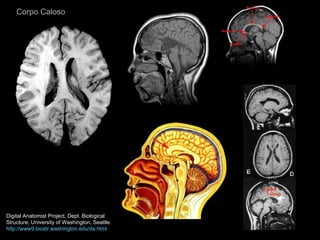

Corpo Caloso Digital Anatomist Project, Dept. Biological Structure, University of Washington, Seattle. http://www9.biostr.washington.edu/da.html

Corpo Caloso DigitalAnatomist Project, Dept. Biological Structure, University of Washington, Seattle. http://www9.biostr.washington.edu/da.html